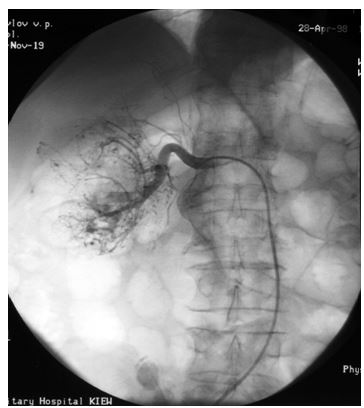

3. Гемзар может быть составным компонентом смеси, вводимой при химиоэмболизации. Применяется 1–1,5 грамма Гемзара в сочетании с липоидолом или другими компонентами.

Рентгенограмма химиоэмболизации метастазов в печень.